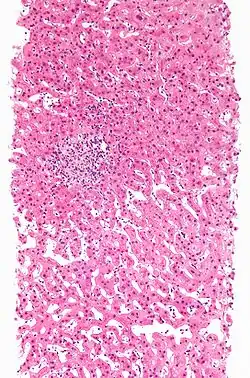

Hepatitis

Hierbij gaat de sterfte van de levercel (hepatocellulaire necrose) gepaard met een ontsteking. Er zijn drie soorten chemische hepatitis.

- Hepatitis A: 'virale' hepatitis. de meest voorkomende is de vorm die onder de microscoop sprekend op hepatitis door een virus lijkt. Oorzaken zijn onder andere halothaan, isoniazide of fenytoïne.

- Hepatitis B: bij focale of non-specifieke hepatitis vind je bij de ontstoken gebieden verspreide haardjes van celnecrose. Een van de mogelijke oorzaken kan acetylsalicylzuur zijn.

- Hepatitis C: chronische hepatitis lijkt klinisch, serologisch, en onder de microscoop sterk op auto-immuunhepatitis. Oorzaken zijn onder andere: alfamethyldopa en diclofenac.